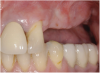

A 62-year-old woman was referred for fixed tooth replacement of the missing maxillary left cuspid, bicuspids, and first molar (Figure 11). Clinical and CBCT evaluation revealed an almost fully pneumatized maxillary left sinus along with alveolar width deficiency. The treatment plan called for a four-unit, implant-supported splinted fixed bridge. A left sinus augmentation along with a ridge split and interpositional bone graft consisting of rhBMP-2/ACS (INFUSE Bone Graft) and mineralized allograft (MinerOss) covered by a dense porous polyethylene mesh (Medpor®, Stryker, www.stryker.com) were done simultaneously (Figure 12, Figure 13 and Figure 14). Six months later, a follow-up CBCT revealed a well-incorporated graft with adequate bone volume and density for implant placement (Figure 15 and Figure 16). Final bridge fabrication followed 3 months later (Figure 17 and Figure 18).

Figure 11  Edentulous left posterior maxilla with alveolar ridge deficiency.